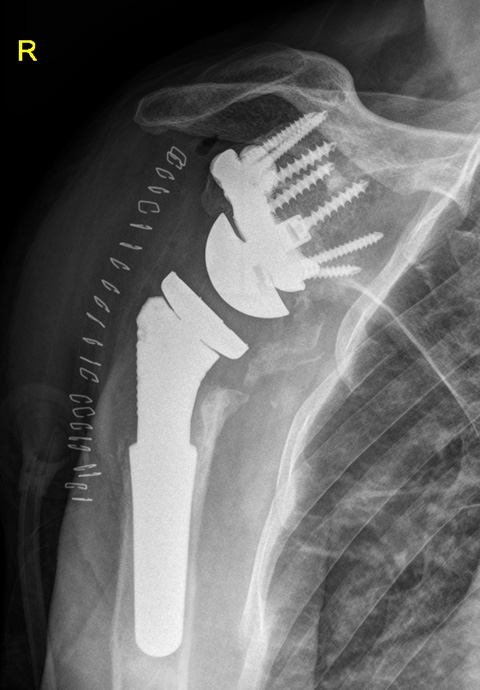

Post-op

Implants used:

- customLINK implant was a perfect fit

- Stable fixation of glenoid with seven bone screws

- Eccentric Glenosphere 42 mm / 4mm

- Modular Revision Stem, 75 mm length, size 24 mm

- Proximal Body, size L, height +5 mm

- Reverse Humeral Tray, neutral

- Reverse Humeral Insert, UHMWPE, dia. 42 mm, height 6 mm, 10° inclined